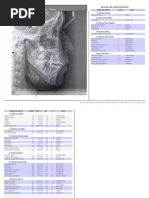

Análisis de Ricketts

CAMPO I PROBLEMA DENTARIO NORMA PACIENTE

1.-Relación Molar -3+-3 mm

2.- Relación Canina -2+-3 mm

3.- Overjet incisivo 2.5+-2.5 mm

4.- Overbite incisivo 2.5+-2.5 mm

5.- Extrusión de incisivo inferior 1.25+-2 mm

6.-Angulo interincisal 130°+-10°

CAMPO II MAXILO MANDIBULAR

7.-Convexidad facial 2+-2 mm

8.-Altura facial inferior 47°+-4°

CAMPO III DENTOESQUELETAL

9.- Posición molar superior Edad +3+-3mm

10.-Inclinación incisivo superior 28°+-4°

11.-Protrusión incisivo superior 3.5+-2mm

12.- Inclinación incisivo inferior 22°+-4°

13.-Protrusión incisivo inferior 1+2mm

14.-Plano oclusal a rama mandibular 0+-3 mm

15.-Inclinación plano oclusal 22°+-4°

CAMPO IV PROBLEMA ESTÉTICO

16.-Protrusión labial -2+-2 mm

17.-Lontigud Labio superior 24+2 mm

18.-Comisura a plano oclusal -3.5 mm

CAMPO V RELACIÓN CRANEOFACIAL

19.-Profundidad facial 87°+-3°

20.-Eje facial 90°+-3°

21.-Cono facial 68°+-3.5°

22.- Ángulo Plano mandibular 26°+-4°

23.-Profundidad Maxilar 90°+-3°

24.-Altura Maxilar 53°+-3°

25.- Plano palatal 1 +-3.5º

CAMPOVI ESTRUCTURAL INTERNO

26.-Deflexión craneal 27º+-3º

27.-Longitud craneal anterior 55mm+/-2.5

28.-Altura facial posterior 55+-3mm

29.-Posición de la rama 76º+-3

30.- Localización de porión -39mm+-2mm

31.- Arco mandibular 26+-4°

32.- Longitud del cuerpo mandibular 65+-2.7 mm